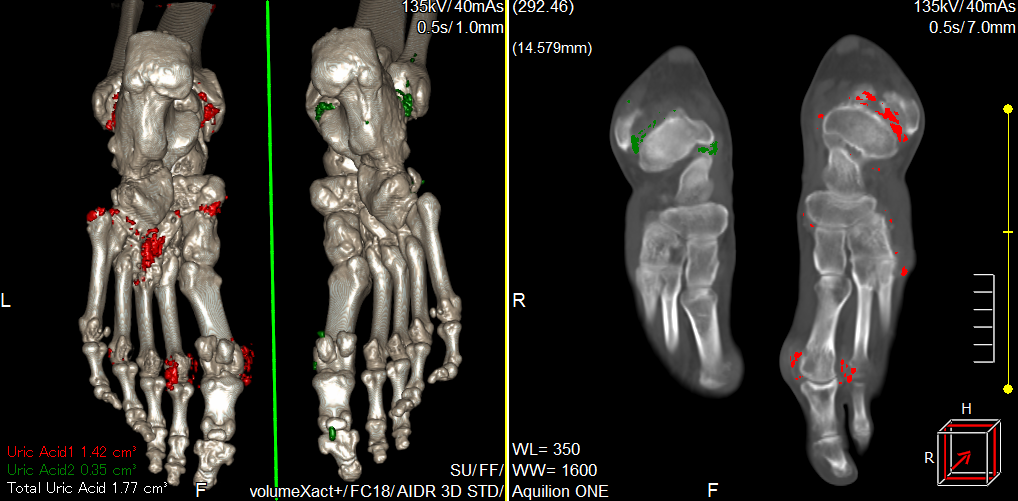

二、能谱痛风分析

用于痛风病的早期发现和诊断,能够明确显示尿酸盐结晶或结石 ,可以发现刚刚形成的尿酸盐结晶微粒,得到尿酸盐结晶数量、大小、位置等全面信息 ,显示尿酸盐结晶、结石对周围关节、软组织有无影响,有无骨质破坏。